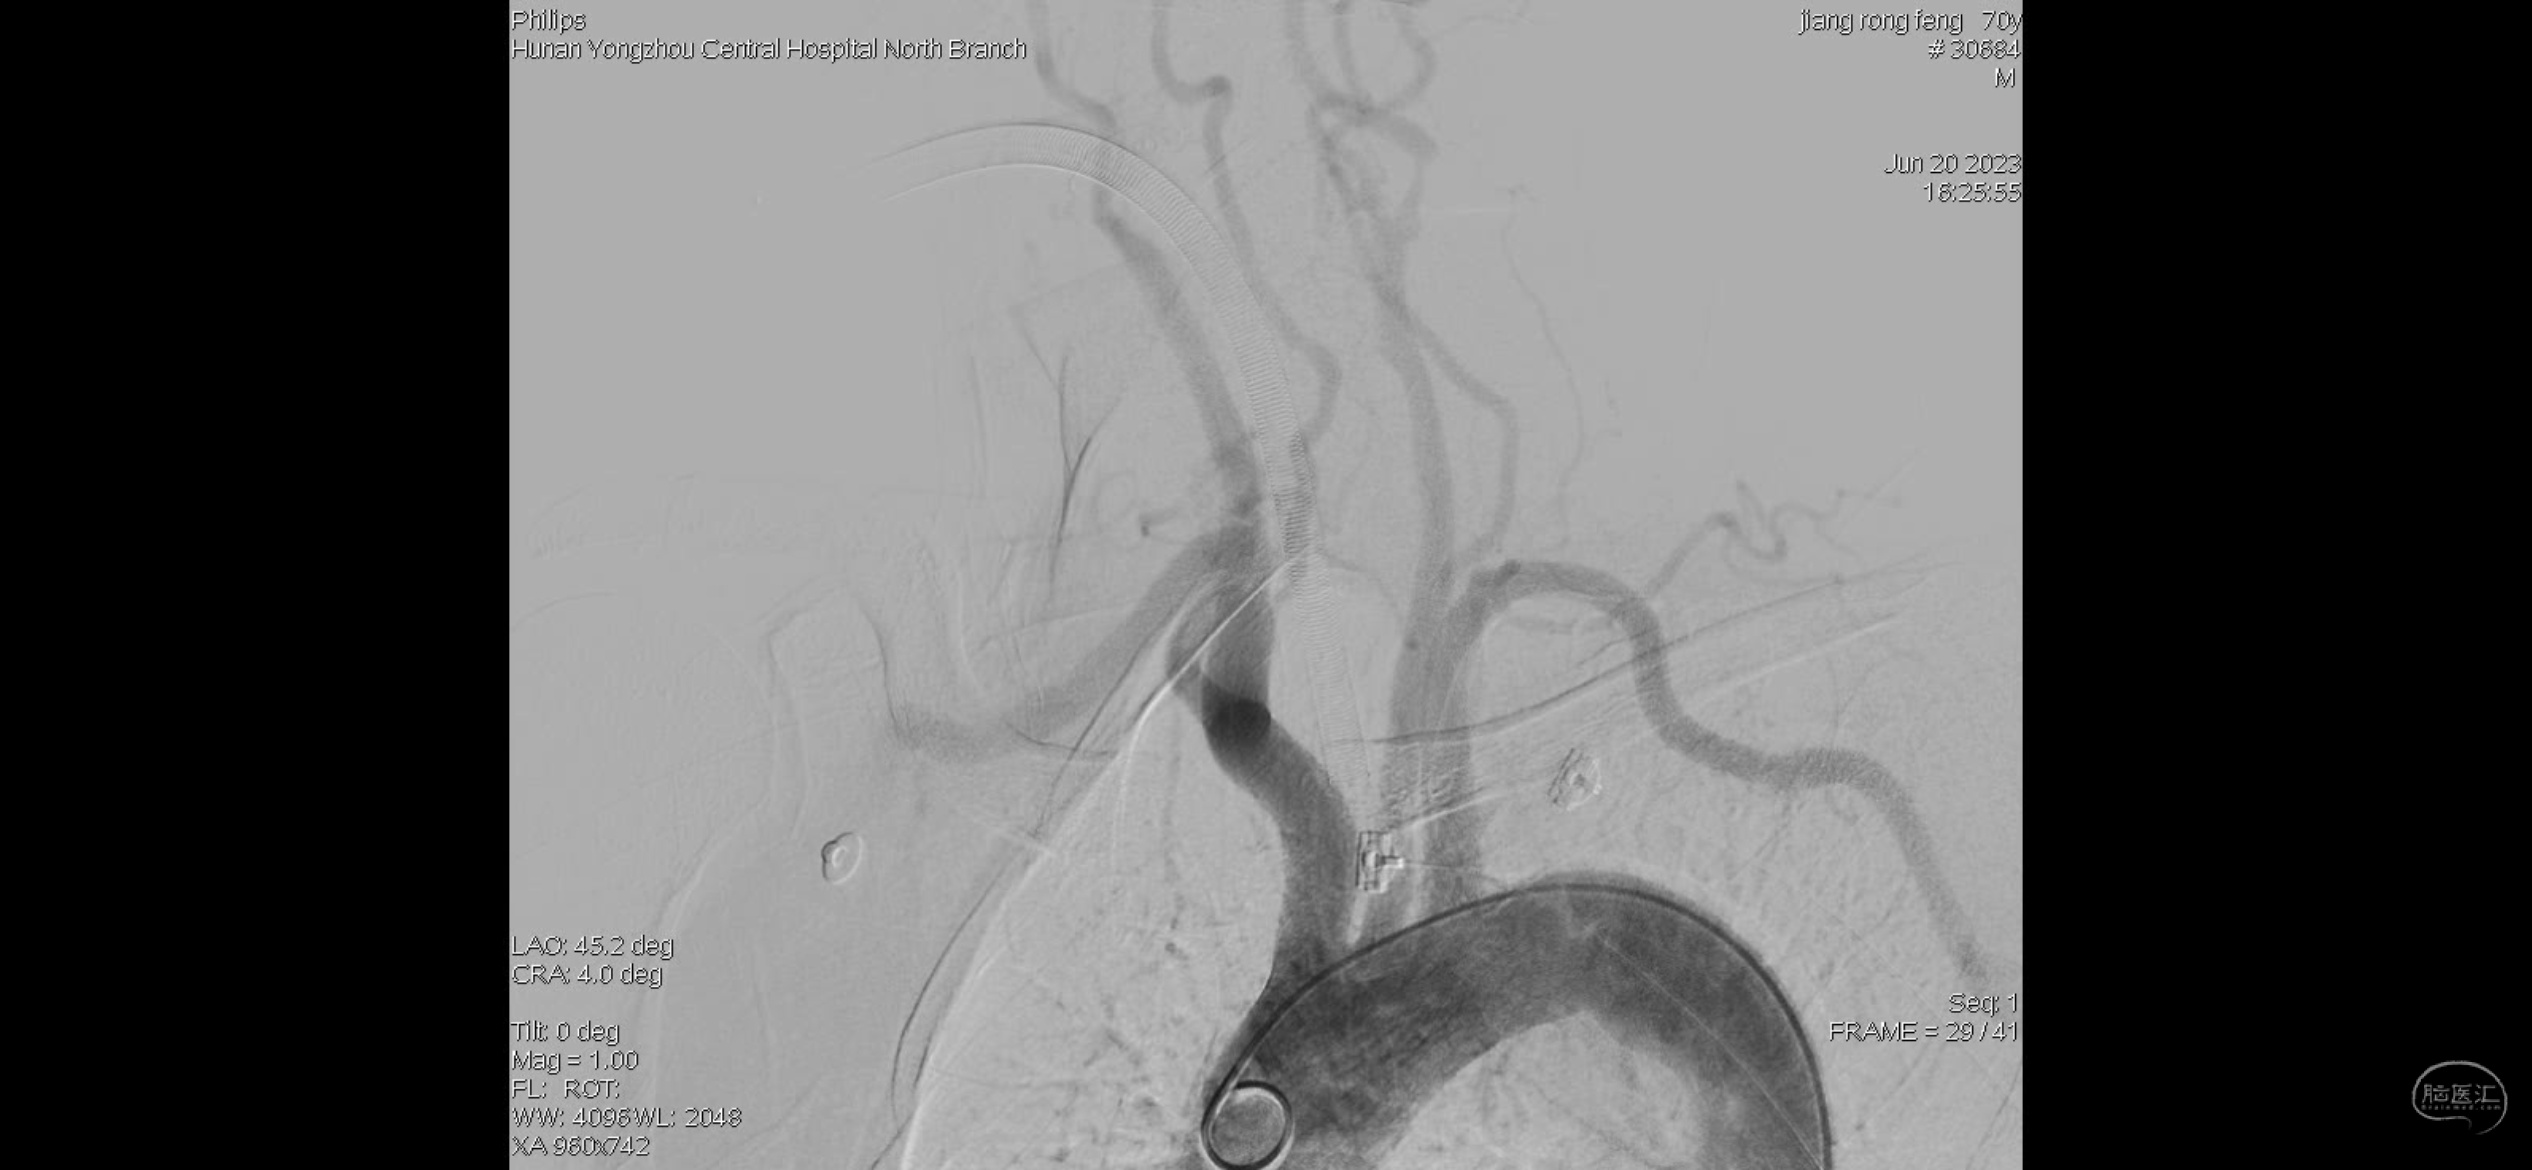

主动脉弓造影提示右侧颈内动脉闭塞。

右侧考虑颈内动脉C1段重度狭窄合并急性闭塞,眼动脉反流显影部分血管,右侧M1分叉部急性闭塞,右侧大脑前血流考虑血流灌注不足影响,且合并A2狭窄。